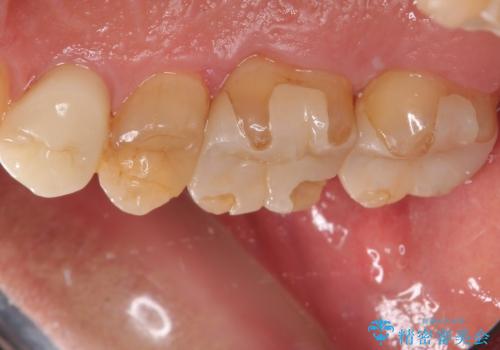

- 食事中に歯が欠けてしまった事を主訴に来院された患者様です。

小臼歯が広範囲に欠けてしまっています。

部分的な詰め物では再びかけてしまうリスクが高いため、オールセラミッククランにて補綴治療をすることとしました。

精度の高い被せものは二次う蝕のリスクが低いです。